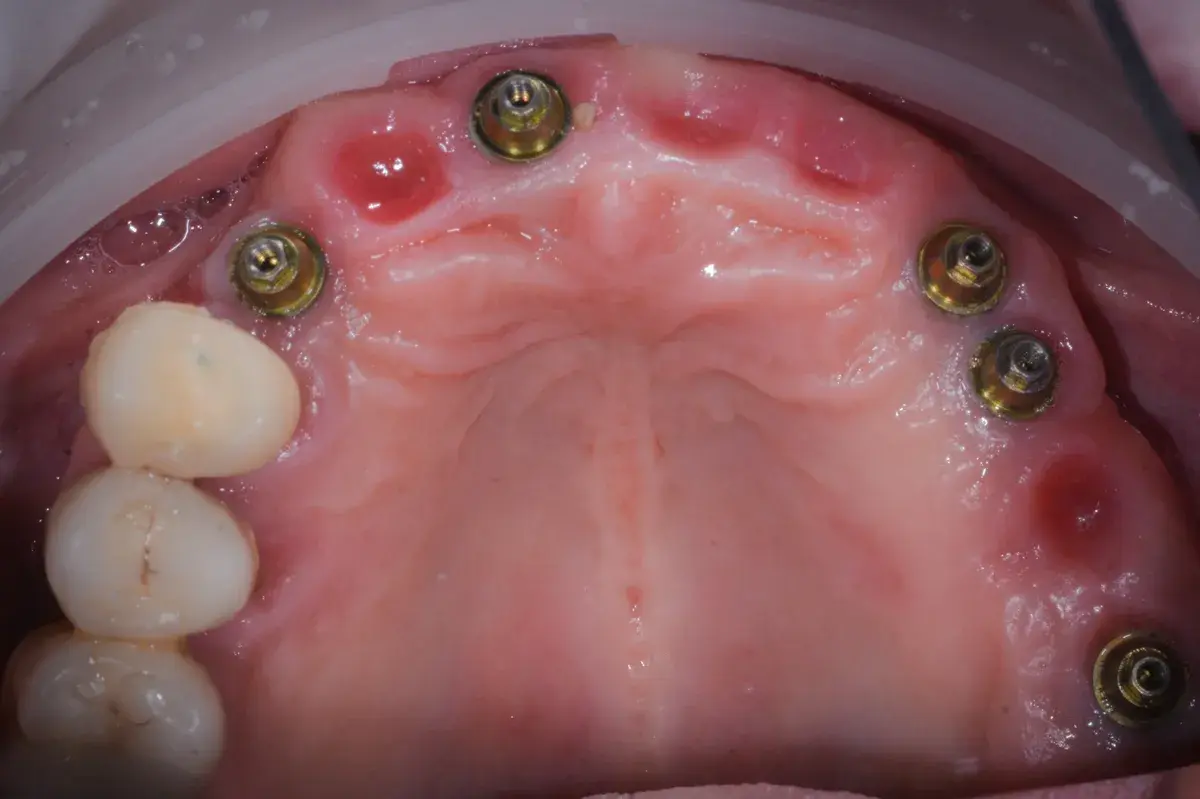

Caso clinico di carico immediato su rialzo crestale del seno mascellare con espansori. Espansione apicale, stabilità >50 Ncm, provvisorio immediato e co...

Paper 2024 su Gingival Open-Wound Technique: "innovazione" o riscoperta? Dr. Bruschi documenta guarigione per seconda intenzione nell'implantologia da...

Scopri come il tuo corpo guarisce naturalmente senza suture. La guarigione per seconda intenzione: il processo che rigenera osso e tessuti per impianti ...

Scopri come funziona l'implantologia a carico immediato, quando è possibile applicarla e quali vantaggi offre. Guida del Dr. Ernesto Bruschi.